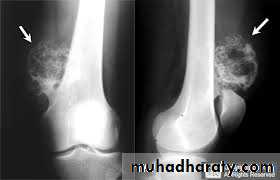

show a radiolucent area situated eccentrically at the end of a long bone and bounded by the sub- chondral bone plate.

The endosteal margin may be quite obvious, but in aggressive lesions it is ill-defined.

X-rays42

The Centre sometimes has a soap-bubble appearance.

The cortex is thin and sometimes ballooned. aggressive lesions extend into the soft tissue.43

The appearance of a ‘cystic’ lesion in mature bone, extending right up to the subchondral plate, is so characteristic